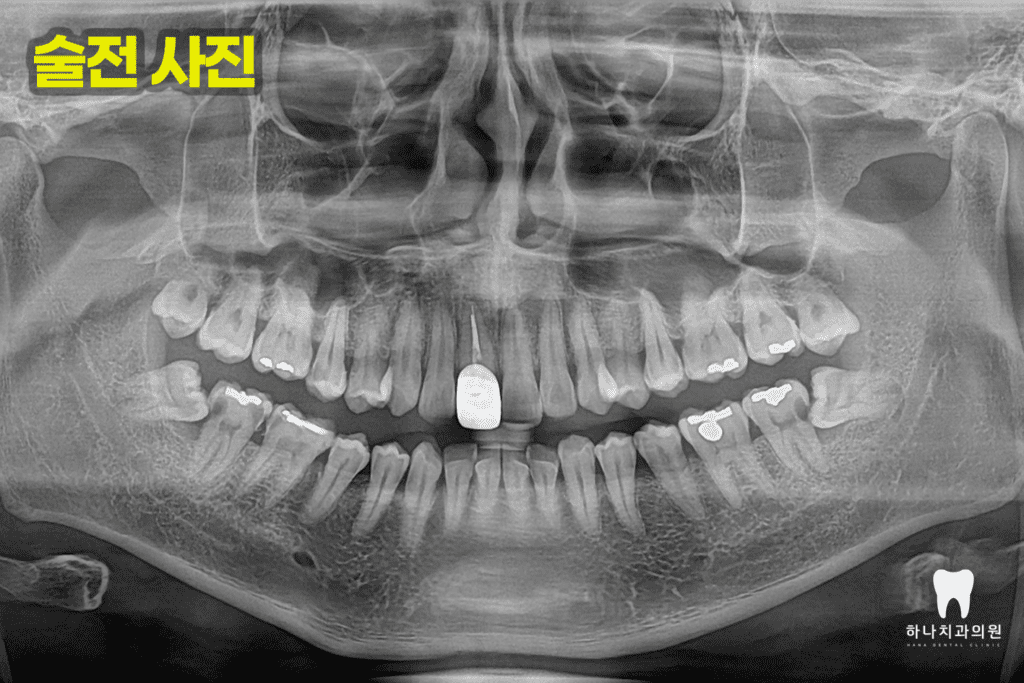

위 환자분께서는 30대 남성분으로

울산삼산동치과에 내원하셔서

진료받으신 경험이 있으신 배우자분의

추천으로 내원해 주셨는데요.

양쪽 어금니가 너무 아프고, 씹지도 못하신다며

치과가 무서워서 어렸을 때 말고는

와보신 경험이 없다고 말씀해 주셨습니다.

양쪽 아래 수평으로 매복되어 있는

사랑니가 관리되지 않아

바로 앞의 큰 어금니 뒤쪽으로

큰 우식을 공통적으로 가지고 있는

모습을 확인할 수 있었는데요.

오른쪽의 경우, 앞쪽에도 우식이

많이 진행된 상태였습니다.

따라서 양쪽에 매복되어 있는 사랑니를

발치하는데 심한 우식이 진행된 오른쪽의 경우

발치 후 임플란트, 왼쪽의 경우는 자연치 크라운을

진행하시기로 계획을 수립하였습니다.

더불어 증상을 보이는 왼쪽 아래

가장 안쪽 어금니는 신경치료와 크라운,

양쪽 위 두 번째 작은 어금니 인접면의 우식은

진행이 심한 오른쪽의 경우 신경치료 및

포스트, 코어, 크라운을 진행하고

왼쪽의 경우 인레이 수복으로

계획을 하였습니다.